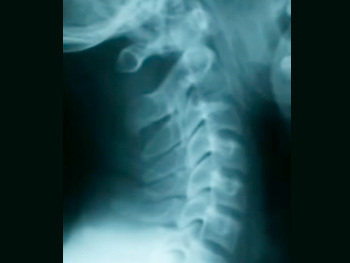

ストレートネックで起こる頭痛と肩こり

ストレートネックは頸椎のカーブ(前彎)が無くなりストレートになった状態でうつ向く姿勢が長時間続く人に多く、最近ではスマホを長時間見ることで首に負担がかかりストレートネックになっている人もいます。

*正常な頸椎のカーブ

*ストレートネック(カーブ無くが真直ぐ)

長年首に負担をかけた状態を放置すると前のカーブが無くなり頚椎がストレートになり肩こりや頭痛、慢性頭痛から全身の色々な症状を引き起こし、年をとるごとに頸椎が変形し悪化していくので早めに対処することが大切です。

*後方に彎曲する頸椎